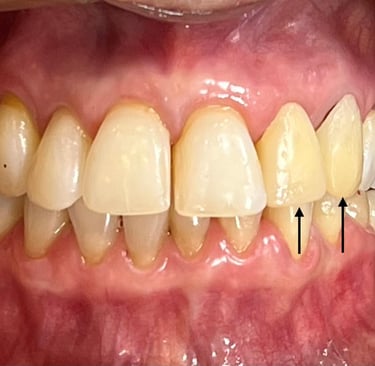

Coroas em Dissilicato de Lítio

Todos os caso a seguir estão associadas a clareamento dentário

Cirurgia de aumento de coroa clínica antes das coroas

Caso que demonstra a vantagem da integração de diversas áreas da odontologia, unindo cirurgia, periodontia, prótese e estética para alcançar resultados funcionais e harmônicos.

Antes

Depois